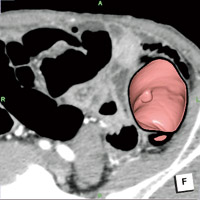

「ziostation2」の大腸解析ソフトウェアは、当センターとザイオソフト社が共同で開発を進めてきました。中でも、画像表示法の1つである仮想展開画像(Virtual Gross Pathology:VGP)に重点をおいてきました。VGPでは、腸管内腔面を1画面に表示できるため、従来の仮想内視鏡(VE)像と比べてきわめて効率的に大腸全体の観察が可能です。大腸には屈曲やヒダが多く、画像の歪みが生じやすいため、それが診断において問題となります。しかし、ziostation2では歪みが最小限に抑えられ、またここ1〜2年で画質も飛躍的に改善されました。結腸紐や半月ひだ、ハウストラなどの描出の進歩は著しく、VE像により即した状態で観察可能であり、ziostation2は臨床的に高いレベルに仕上がっています。

また、画像処理のプロセスも大幅に改良され、ストレスなく高速に各画像表示法を活用できるようになった点も、非常に大きな進歩です。CTCの診断にあたっては、VGPのほか、魚眼方式で観察することができるVEスコープビュー表示、air enema表示などを使用しますが、これらをいかに組み合わせて読影するかが重要なポイントとなります。われわれも当初は、1症例あたりの読影に約30分かかっていましたが、VGPに慣れるに従って診断効率がどんどん向上し、現在では10分程度にまで短縮しています。スクリーニングでは、術前診断と異なり、いかに正確に病変を拾い上げ、存在診断を行うかが重要になりますので、粘膜面全体を一瞬で観察できるVGPはきわめて有用です。

ziostation2では、VGP、VE像、air enema像がすべてリンクしているため、VGPで病変が疑われる部位を画面上でクリックすれば、ほかの画像の同じ部位に印が表示されます。VE像とMPR像との合成画像の質も非常に高く、VGPで印をつけた部位を断層像で詳細に評価することも可能です。当センターでは、実際にこのような診断プロセスを構築することで、読影時間の短縮につながりました。将来的にはVGPを中心に、1症例あたり数分で診断できる診断プロトコルを構築したいと考えています。